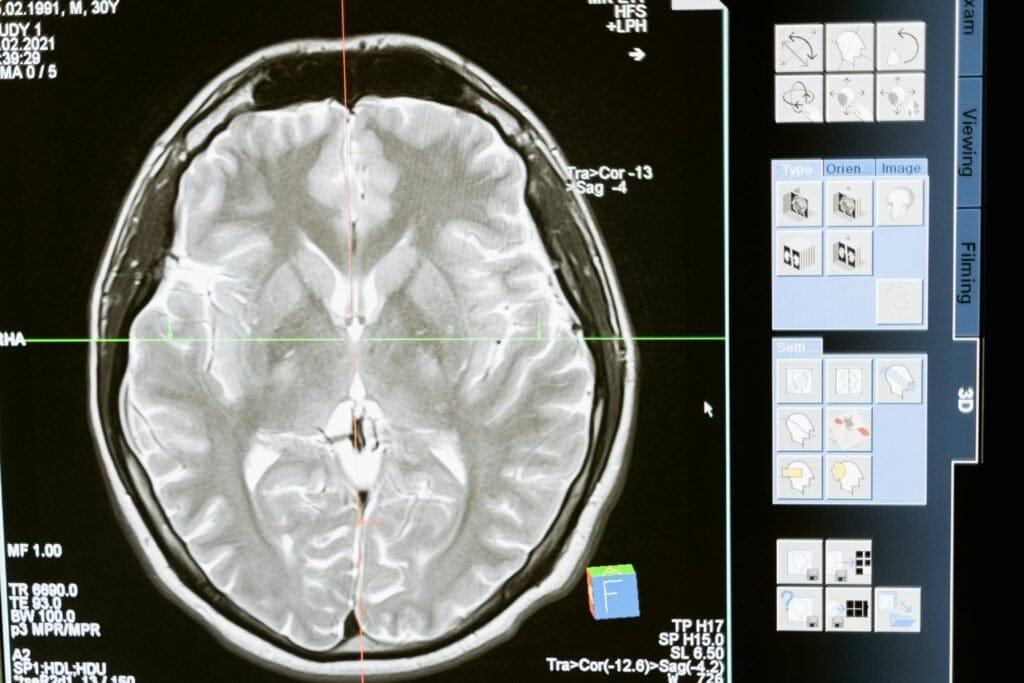

La inteligencia artificial ha comenzado a transformar la investigación del Alzheimer, ofreciendo herramientas capaces de acelerar el entendimiento de la enfermedad. Sistemas como AlphaFold permiten visualizar estructuras tridimensionales de proteínas, lo que antes era un reto casi inabordable. Esta capacidad ha revolucionado la forma en que los científicos analizan la acumulación de placas amiloides y ovillos neurofibrilares, responsables de la muerte progresiva de neuronas.

Con la IA, es posible diseñar tratamientos más precisos y personalizados, así como estudiar mutaciones genéticas que afectan el plegamiento proteico. La tecnología abre la puerta a terapias dirigidas, enfocadas en la causa raíz, y no solo en los síntomas, beneficiando a millones de personas en el mundo.